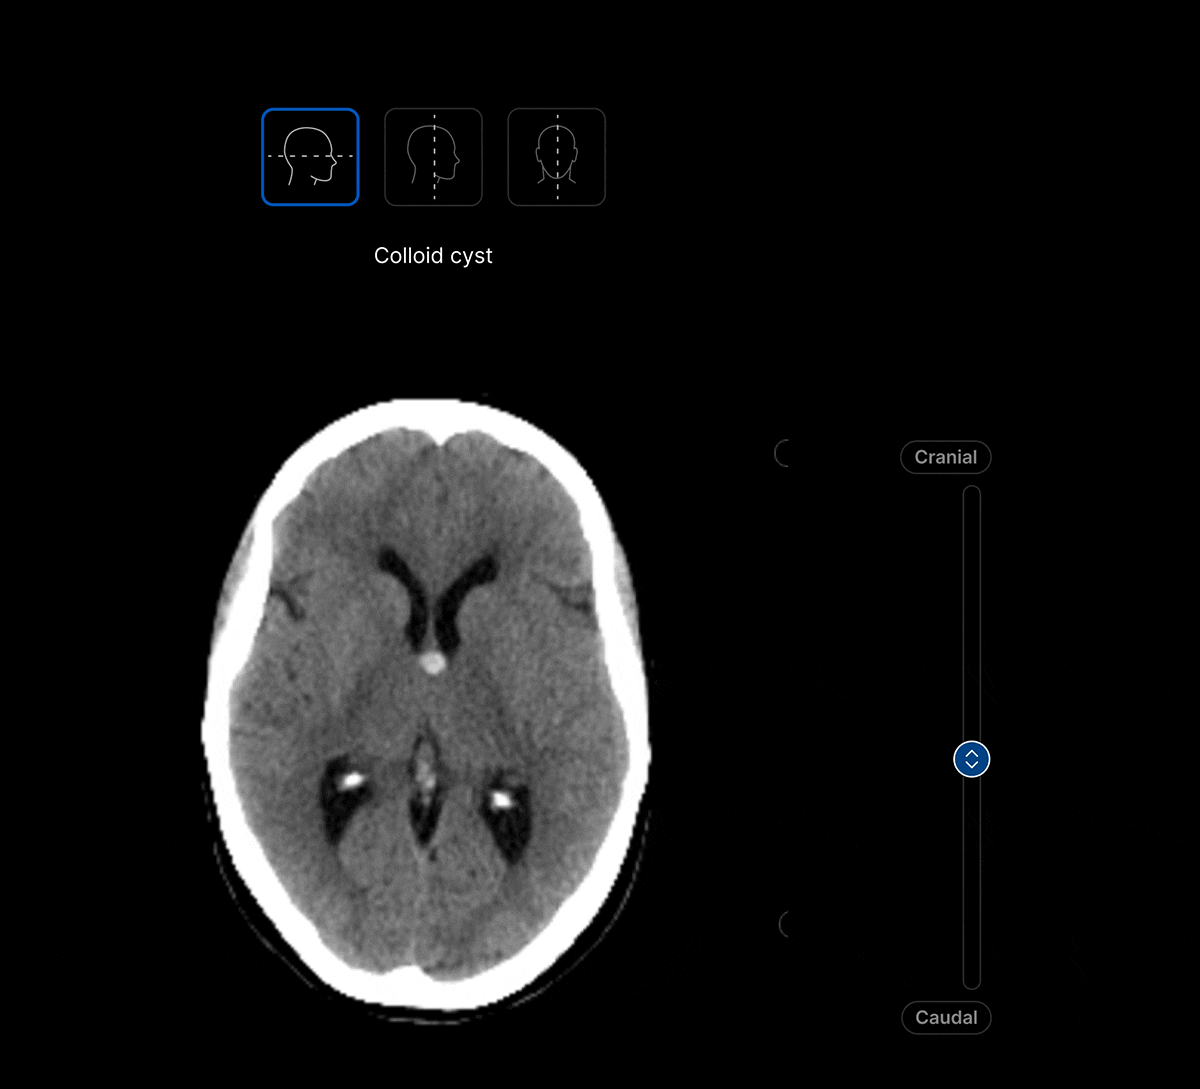

Harrison.ai CT Brain (CTB) is our comprehensive imaging AI solution for non-contrast head CT studies that detects up to 130 findings in under 90 seconds, boosting emergent and incidental capture while surfacing urgent cases for review first – all within the workflow you’re used to.

The UI integrates seamlessly with PACS/ RIS, displaying a resizable, no-click overlay window with findings and localisation.

Customisable thresholds, for individual findings (to optimise for sensitivity / specificity) to tailor the workflow to your clinical setting or population.

Maximise clinical value and simplify your workflow with a single comprehensive solution for non-contrast head CT studies, identifying up to 130 findings. No need to juggle multiple solutions for different findings.